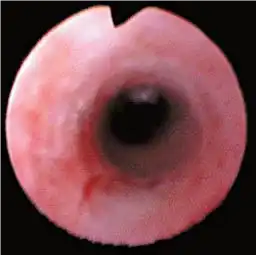

Evolutiontip与5.3 Fr小直径

Evolutiontip是一种创新的适应范围头端设计,可与角度方向对齐,使插入更加平滑,同时保持高清图像质量和治疗能力。由于5.3 Fr头端直径,可插入性显着提高。